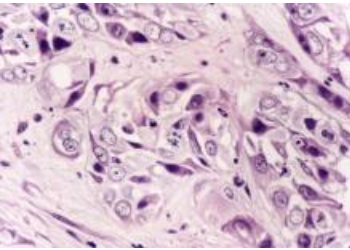

肿瘤多为有形肿块,坚硬难移,软坚散结是必用之法。抗癌消瘤中药系列法中蓖麻子、乳浸、厚朴等具有软坚散结、消瘀除积作用。软坚散结药物抗肿瘤主要在于直接杀伤癌细胞。病理学及超微结构观察表明,其成份对癌细胞具有较强杀伤破坏作用,直接作用于癌细胞膜系结构,使细胞膜溶解破碎,粗面内质网扩张,线粒体肿胀,空泡化,使癌细胞整体崩解碎裂。

四、软坚散结